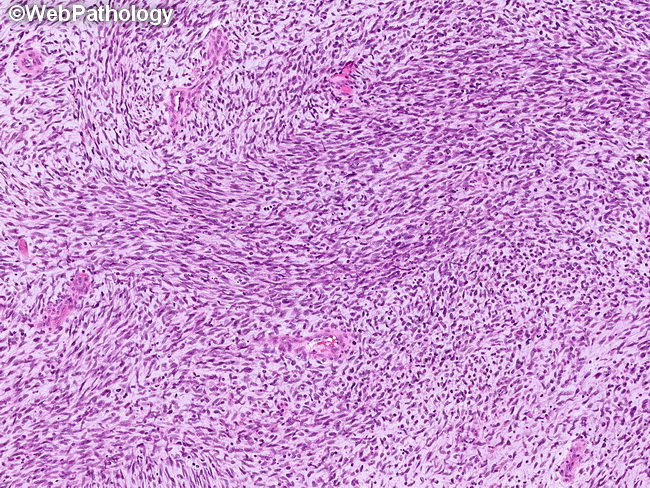

Webpathology.com: A Collection Of Surgical Pathology Images

www.webpathology.com

www.webpathology.com

orbit rhabdomyosarcoma embryonal webpathology rms comments

Rhabdomyosarcoma (orbit). Rhabdomyosarcoma pathophysiology. Orbit rhabdomyosarcoma embryonal webpathology rms comments